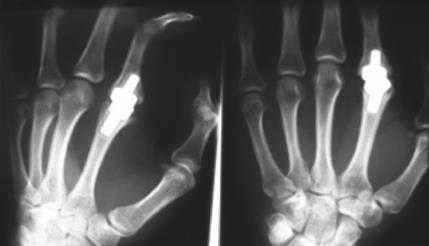

Эндопротезирование пястно-фалангового сустава кисти

Эндопротез пястно-фалангового сустава представляет собой несвязанный эндопротез, состоящий из проксимального и дистального компонентов. Материалом изготовления служит циркониевая керамика.

- Идиопатические и посттравматические артрозы;

- Дегенеративные и постинфекционные артрозы;;

- Костные анкилозы;

- Неправильное положение (вследствие артроза, травмы);

Эндопротез искусственный материал, который может со временем разрушаться, поэтому необходима ежегодная консультация оперирующего врача или ассистента его замещающего, чтобы своевременно устранить возможные осложнения.